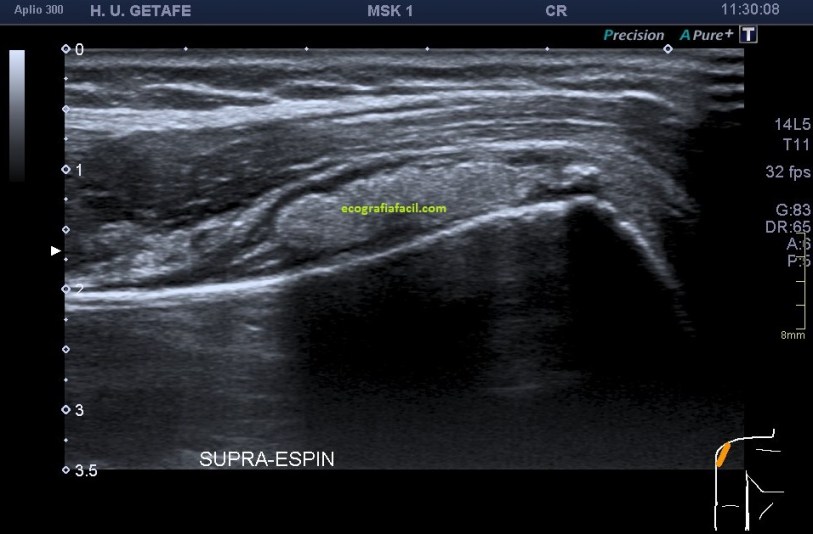

El tendón extensor es una ecoestructura muy fina, que puede pasar desapercibida si no tenemos una alta calidad de imagen, en la imagen 4 lo tienes delimitado entre dos líneas rosas, por si en la imagen 3 te había costado situarlo, repito, fundamental en este estudio su caracterización.

La anatomía de la ecoestructura, sobre todo de la imagen 3 deja muy a las claras uno de los objetivos del estudio, que era valorar la independencia del tendón extensor del dedo respecto del tumor, es decir, que el tendón, hueso y piel estuviesen indemnes como así fue.